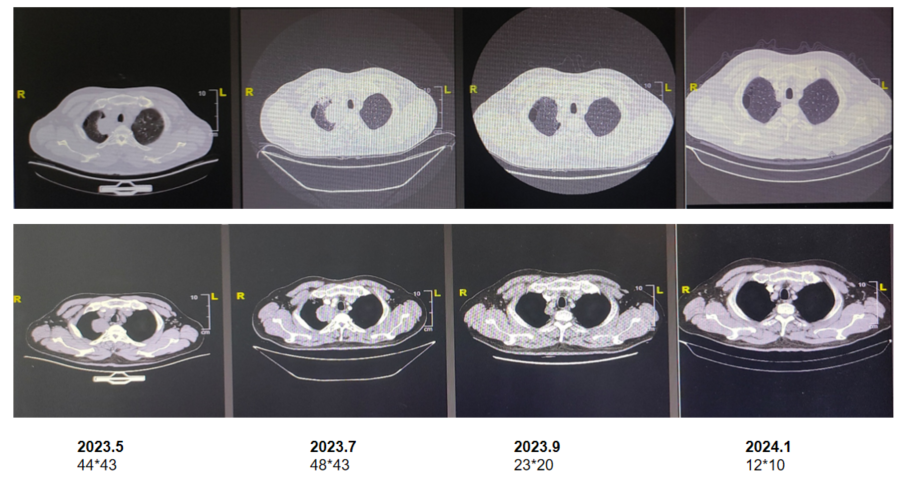

3) 免疫治疗:髂骨局部问题得到快速控制后,于5月29日开始按计划行PD-1抑制剂联合化疗治疗,免疫联合化疗3周期后(2023年7月)CT示右肺上叶恶性肿瘤,周围多发炎症;双肺散在微小结节;右侧锁骨上、两肺门及纵隔多发小淋巴结;左第一前肋骨转移可能骨盆多处骨转移可能。随访CT显示患者肺部病灶大小较老片相仿,疗效评估:疾病稳定(SD)。患者疾病症状、指标改善,患者自觉较此前体力有明显改观,结合患者实际情况,综合考虑肺部影像学变化是免疫治疗初期炎症细胞浸润和肿瘤组织坏死水肿导致的肿块一时性增大,故继续维持原方案治疗。

图片3.png

图3. 免疫治疗3周期后胸部CT

4)骨保护药物治疗:2023年7月下旬完成初期免疫联合化疗后,开始行PD-1抑制剂联合培美曲塞维持治疗,同时联合地舒单抗规律骨保护治疗。

5)后续维持治疗与随访:2023年9月,MRI示骨盆仍有多处骨转移,右侧骶骨范围缩小,余同前。原本问题较为严重的髂骨病灶在放疗、免疫联合化疗、骨保护治疗的综合治疗下取得了良好的治疗效果,病灶大幅退缩,患者行动能力得到恢复;CT示右肺上叶肿瘤较前退缩,周围多发炎症较前减轻。右锁骨上淋巴结较前缩小。余双肺多发小结节,较前减少。两肺门及纵隔小淋巴结较前缩小。

图片4.png

图4. PD-1联合培美曲塞、地舒单抗治疗2月后MRI结果

2023年11月30日,CT示原右肺上叶纵隔旁肿块此次呈片状改变,右锁骨上淋巴结较前略缩小。部分椎体及肋骨局灶致密同前。

2024年3月29日,CT示右肺上叶纵隔旁片状影较前略减小,右锁骨上、两肺门及纵隔小淋巴结同前相仿,双肺肺大疱,两肺多发微小结节,部分椎体及肋骨局灶致密同前相仿。

2024年10月10日,CT示右肺MT复查,右肺上叶纵隔少许条状索影同前相仿,右锁骨上、两肺门及纵隔小淋巴结同前相仿,双肺肺大疱同前;部分椎体及助骨局灶致密同前相仿。

2025年4月15日,CT及PET/CT显示原发灶及全身多发转移淋巴结基本消退,全身多处骨转移灶亦明显好转,局部成骨性骨质改变,未见FDG代谢增高,提示骨修复。疗效评估:完全缓解(CR)。